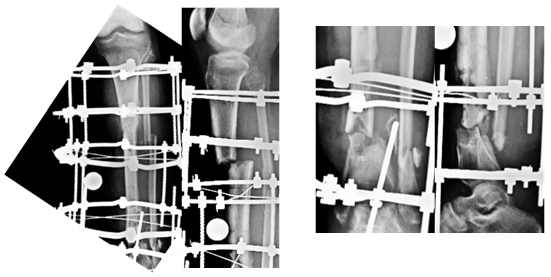

| X-rays at Presentation | ||

| The x-rays showed nonunion at both the upper and lower fracture sites. The lower fracture site showed infection and dead bone. The fixator was not holding the bone fragments in good alignment and the wires were all loose and some of them were infected. | ||